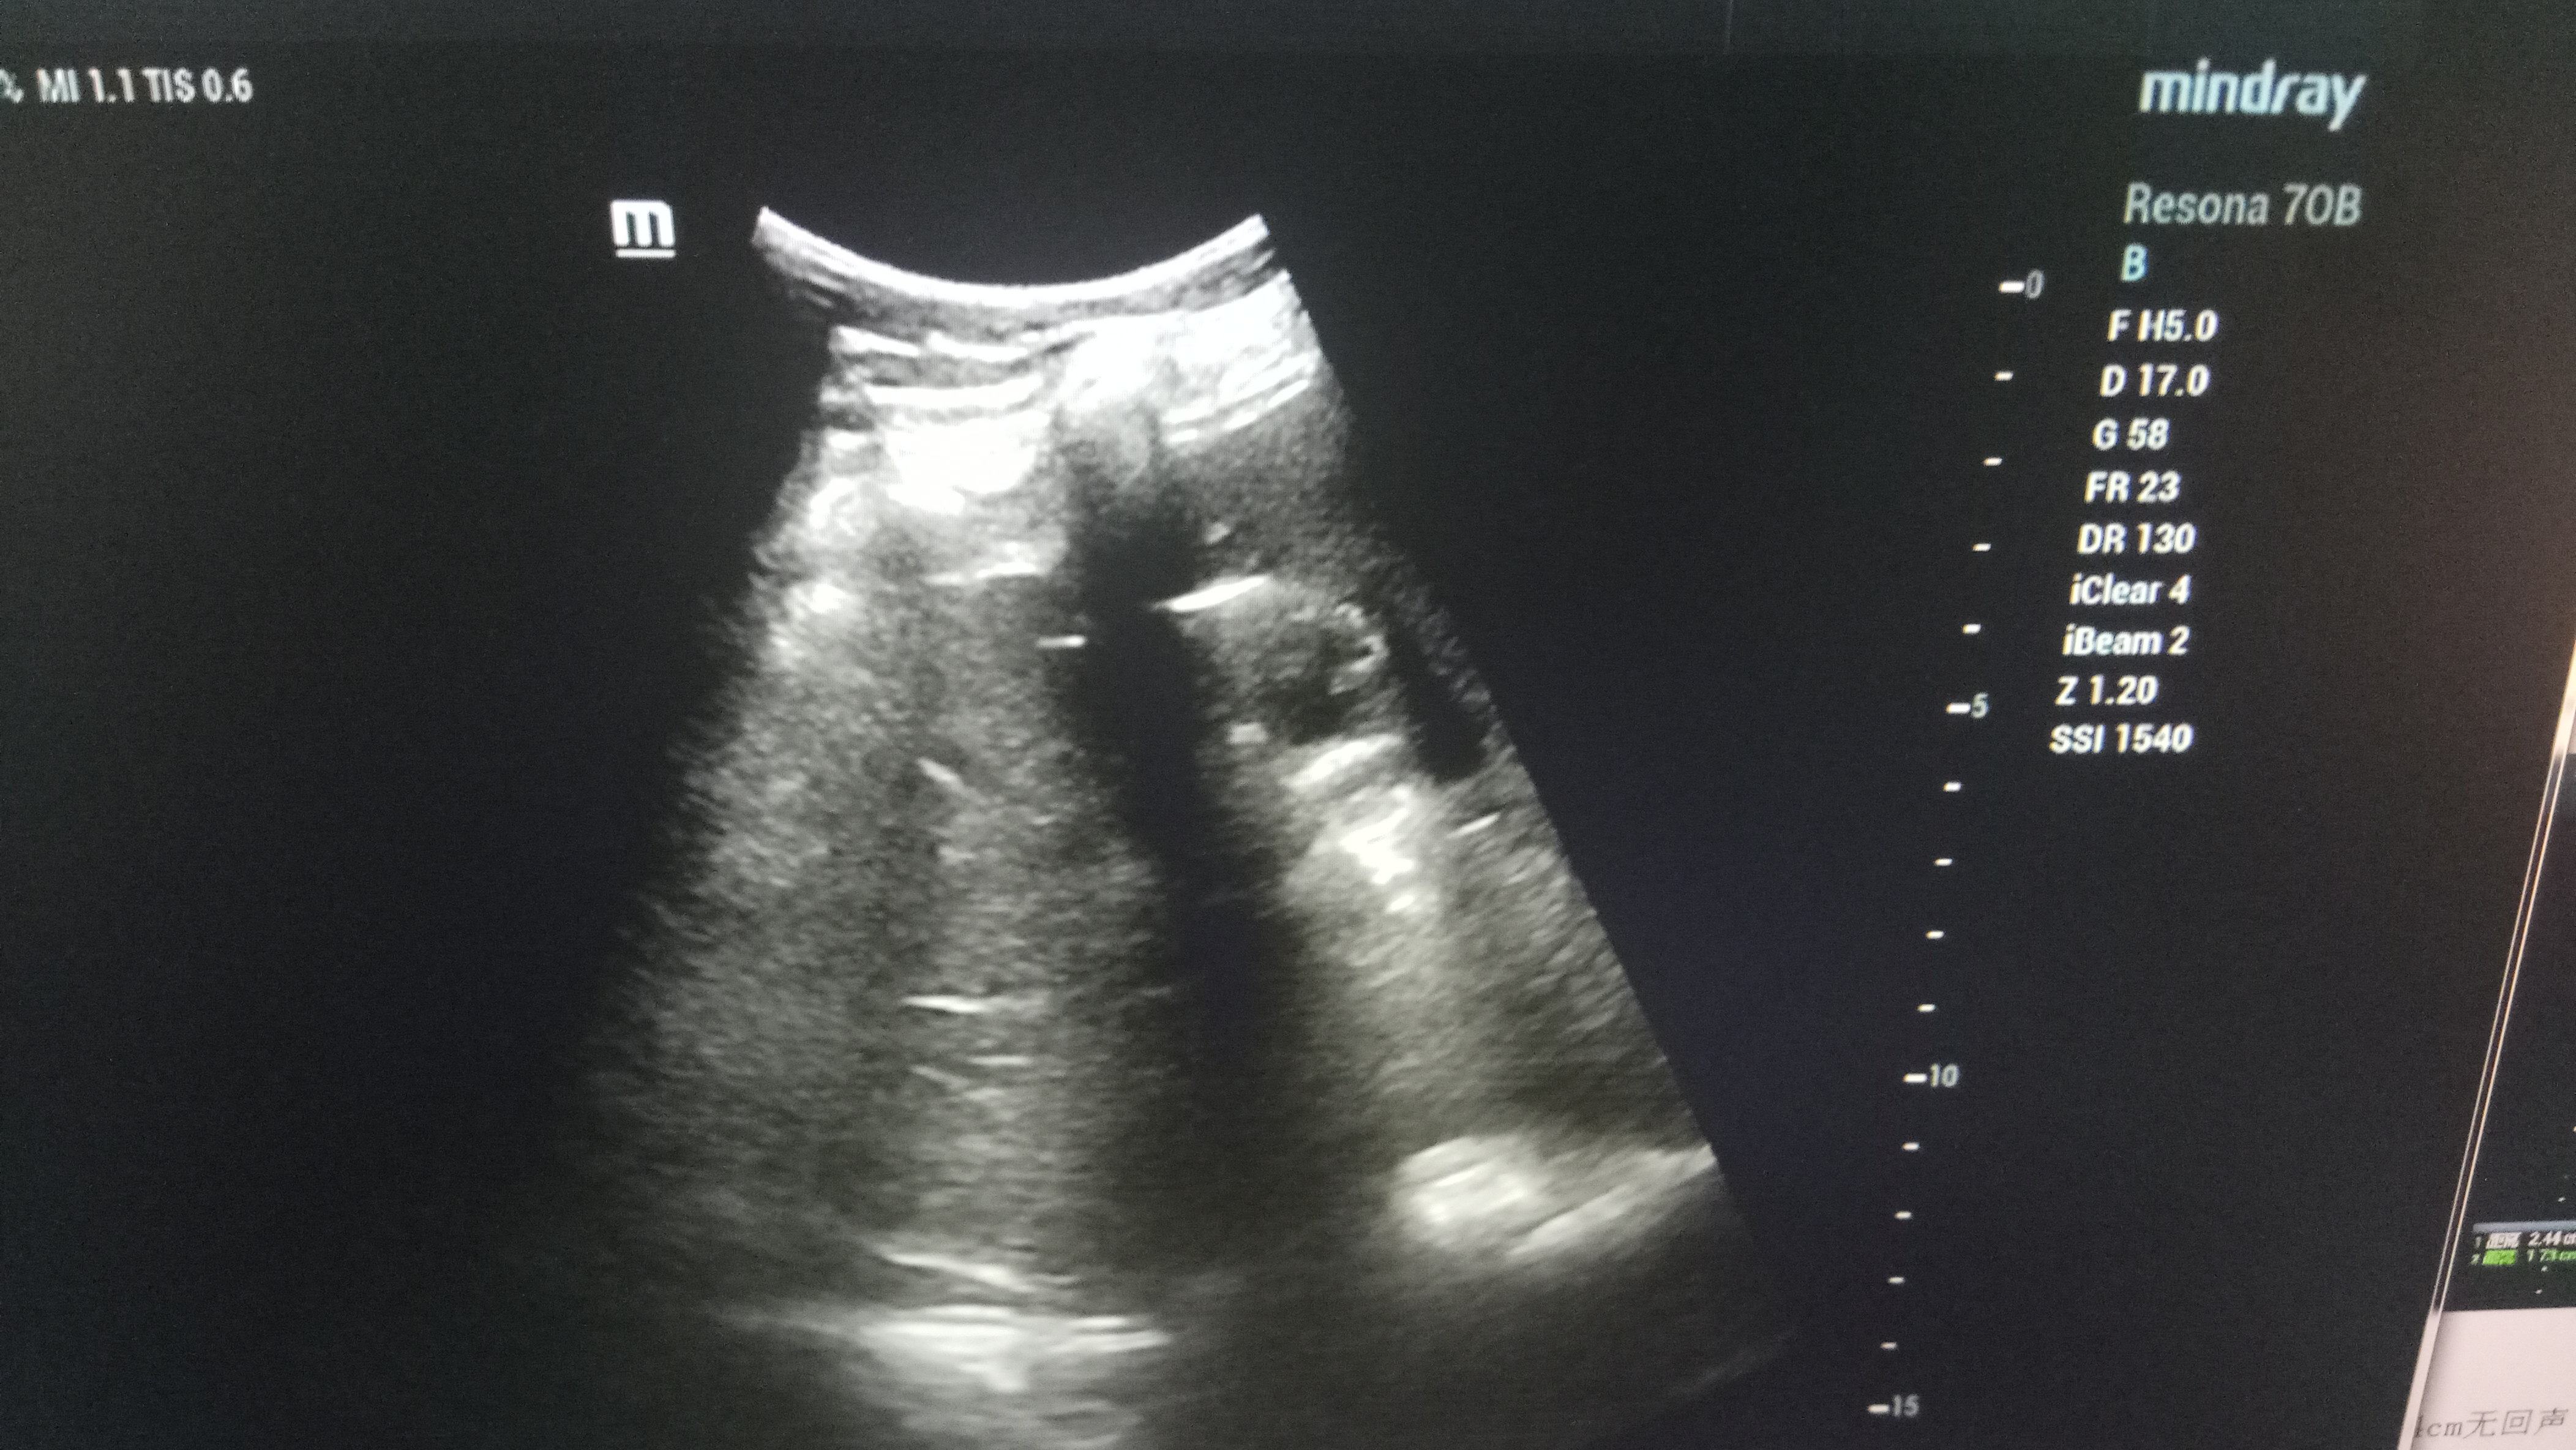

近日,男同视频 超声科在高陵区医院成功开展了一例超声引导下肝囊肿抽吸硬化治疗术。患者前段时间查出肝囊肿,因开腹手术风险性大且痛苦,遂联系了高陵区医院超声科,在男同视频 超声科主任展小军与对口支援医生杨艳秋的紧密配合下,短短30分钟,通过一根穿刺针,直径近7cm的肝囊肿就被完全抽吸硬化完毕,患者生命体征平稳,休息几小时后已活动自如。

超声介入微创诊疗技术是在实时超声的监视和引导下,完成各种穿刺、活检以及抽吸、插管、注药治疗等操作,达到与外科手术相当的效果,具有创伤小、恢复快、无辐射、介入治疗定位精确等优点。可治疗全身各部位囊肿,尤其是巧克力囊肿效果更佳,还有全身各部位肿瘤的活检和治疗,超声引导下微创治疗是未来医学发展方向。